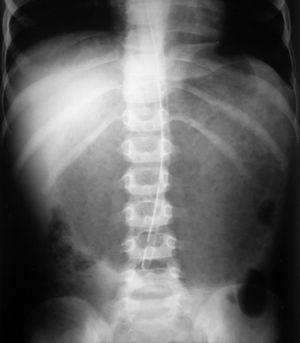

Un niño de 4 años de edad operado de reflujo gastroesofágico 15 meses antes ingresa de urgencia por dolor abdominal, distensión epigástrica por masa palpable, vómitos, deshidratación y afectación grave del estado general, de 10 h de evolución. Dieciocho horas antes había ingerido abundante cantidad de bebidas gaseosas. Acostumbra a ingerir verdura cruda y plastilina. La radiografía simple de abdomen muestra estómago muy distendido, ocupado por contenido con aspecto de bezoar y aparente neumatosis quística (fig. 1). El lavado gástrico evacua gran cantidad de contenido vegetal y líquido oscuro de olor pútrido y pH muy ácido. Veinticuatro horas después la radiografía de abdomen muestra menor contenido gástrico con disección por gas de la pared del estómago (fig. 2). Cuatro días después empeora su estado general y aparece reacción peritoneal. Se realiza laparotomía urgente, y se detecta necrosis extensa de pared gástrica con perforación. Se extirpa la zona necrosada y se anastomosan fórnix y antro preservados. La evolución es buena a corto y largo plazo.

Figura 2. Disección por gas de la pared gástrica.